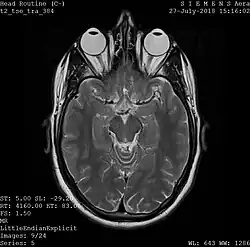

A magnetic resonance imaging instrument (MRI scanner), or "nuclear magnetic resonance (NMR) imaging" scanner as it was originally known, uses powerful magnets to polarize and excite hydrogen nuclei (i.e., single protons) of water molecules in human tissue, producing a detectable signal which is spatially encoded, resulting in images of the body.[12] The MRI machine emits a radio frequency (RF) pulse at the resonant frequency of the hydrogen atoms on water molecules. Radio frequency antennas ("RF coils") send the pulse to the area of the body to be examined. The RF pulse is absorbed by protons, causing their direction with respect to the primary magnetic field to change. When the RF pulse is turned off, the protons "relax" back to alignment with the primary magnet and emit radio-waves in the process. This radio-frequency emission from the hydrogen-atoms on water is what is detected and reconstructed into an image. The resonant frequency of a spinning magnetic dipole (of which protons are one example) is called the Larmor frequency and is determined by the strength of the main magnetic field and the chemical environment of the nuclei of interest. MRI uses three electromagnetic fields: a very strong (typically 1.5 to 3 teslas) static magnetic field to polarize the hydrogen nuclei, called the primary field; gradient fields that can be modified to vary in space and time (on the order of 1 kHz) for spatial encoding, often simply called gradients; and a spatially homogeneous radio-frequency (RF) field for manipulation of the hydrogen nuclei to produce measurable signals, collected through an RF antenna.

Like CT, MRI traditionally creates a two-dimensional image of a thin "slice" of the body and is therefore considered a tomographic imaging technique. Modern MRI instruments are capable of producing images in the form of 3D blocks, which may be considered a generalization of the single-slice, tomographic, concept. Unlike CT, MRI does not involve the use of ionizing radiation and is therefore not associated with the same health hazards. For example, because MRI has only been in use since the early 1980s, there are no known long-term effects of exposure to strong static fields (this is the subject of some debate; see 'Safety' in MRI) and therefore there is no limit to the number of scans to which an individual can be subjected, in contrast with X-ray and CT. However, there are well-identified health risks associated with tissue heating from exposure to the RF field and the presence of implanted devices in the body, such as pacemakers. These risks are strictly controlled as part of the design of the instrument and the scanning protocols used.

Because CT and MRI are sensitive to different tissue properties, the appearances of the images obtained with the two techniques differ markedly. In CT, X-rays must be blocked by some form of dense tissue to create an image, so the image quality when looking at soft tissues will be poor. In MRI, while any nucleus with a net nuclear spin can be used, the proton of the hydrogen atom remains the most widely used, especially in the clinical setting, because it is so ubiquitous and returns a large signal. This nucleus, present in water molecules, allows the excellent soft-tissue contrast achievable with MRI.[13]

A number of different pulse sequences can be used for specific MRI diagnostic imaging (multiparametric MRI or mpMRI). It is possible to differentiate tissue characteristics by combining two or more of the following imaging sequences, depending on the information being sought: T1-weighted (T1-MRI), T2-weighted (T2-MRI), diffusion weighted imaging (DWI-MRI), dynamic contrast enhancement (DCE-MRI), and spectroscopy (MRI-S). For example, imaging of prostate tumors is better accomplished using T2-MRI and DWI-MRI than T2-weighted imaging alone.[14] The number of applications of mpMRI for detecting disease in various organs continues to expand, including liver studies, breast tumors, pancreatic tumors, and assessing the effects of vascular disruption agents on cancer tumors.[15][16][17]